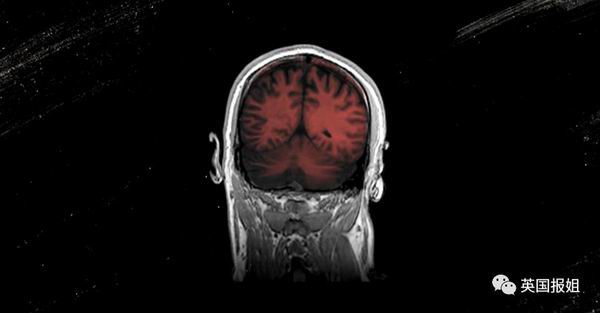

有来自医院机构研究的早期数据表明,所有年龄段的新冠住院患者中,有三分之一表现出谵妄的迹象。其中,三分之二的重症患者都明确患有谵妄症。

相当高的比例引起了医护人员的担忧,由于患有谵妄症,患者变得动弹不得或身体虚弱,进而需要更长的住院时间,导致更多并发症,需要长期护理或发展为认知障碍,包括痴呆等长期治疗的疾病。

但唯一的好消息是,谵妄症有.30-40%的机率是可以预防的。

哈佛医学院的医学教授.Sharon.Inouye.创建了世界上使用最广泛的教程和一项计划来识别谵妄症,已经帮助数百家医院减少了约.40%谵妄症患者。

由于突然讲话不畅和思想混乱,却难以解释;又或者对日常事件、工作以及熟悉的人感到困惑等症状,接近一半的新冠肺炎治愈者无法重新上班。

加拿大神经学家说.:".我们已经知道.ICU.的幸存者很容易认知障碍。目前得到治愈的新冠患者的越来越多。但我不得不说,对他们来说,离开.ICU.并不是结束,只是他们康复的第一步。"